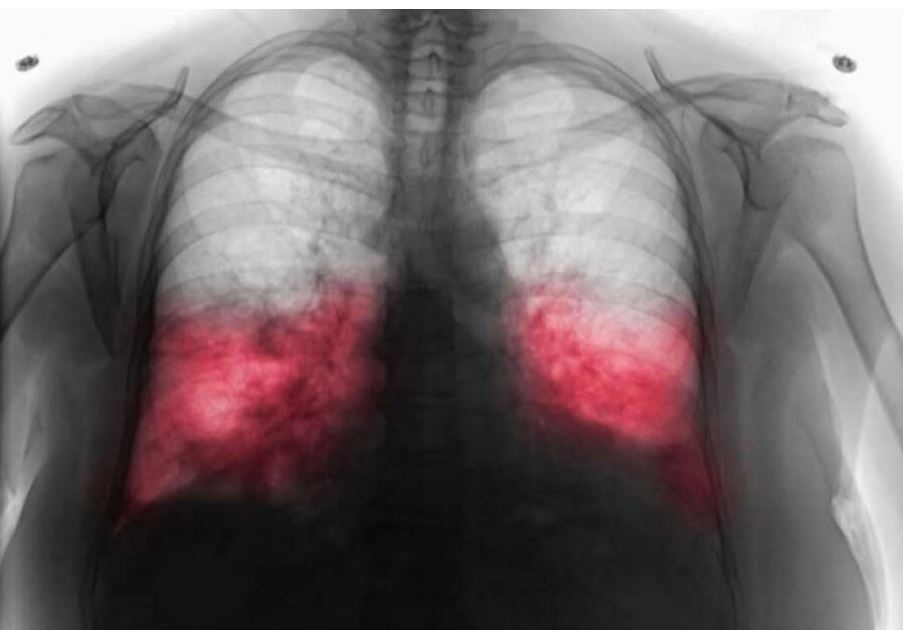

Rendgen pluća (ako je potrebno) kako bi se isključile druge bolesti

Kako se dijagnostikuje?

Dijagnoza hodajuće upale pluća zahteva pomnu analizu simptoma. Ako lekar posumnja na ovu bolest, može da prepiše sledeće korake: